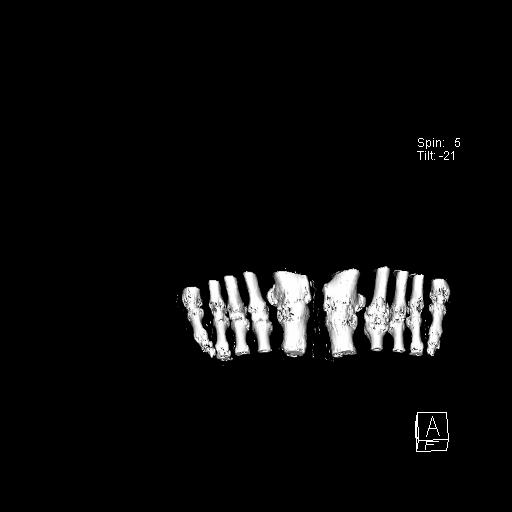

标题: CT13415:M72Y,跖趾关节病变,请会诊 [打印本页]

标题: CT13415:M72Y,跖趾关节病变,请会诊

男72岁左侧跖趾关节肿痛15年,查压痛。

骨软骨瘤可能性大,请上传x光片.

不象软骨瘤,

考虑退行性骨关节病。